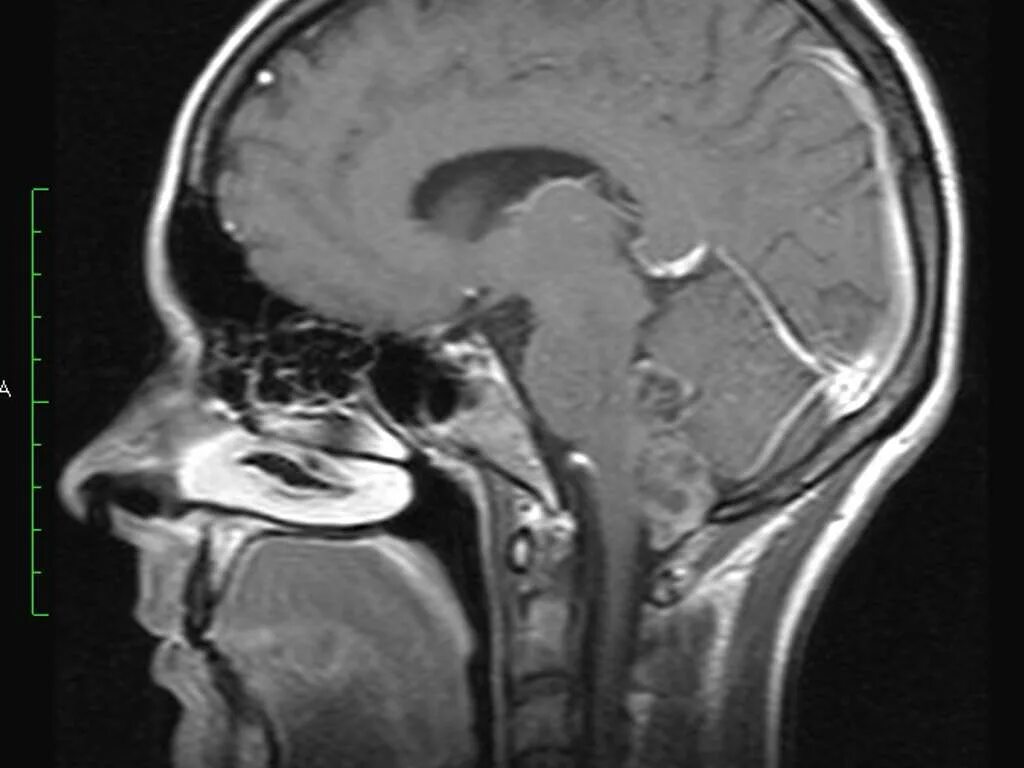

Ретроцеребеллярная ликворная киста